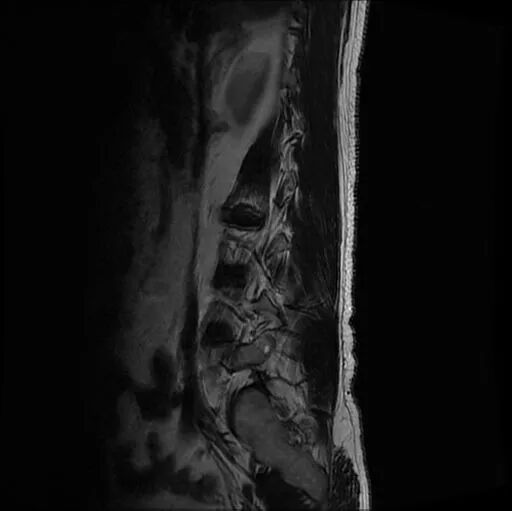

portant; overflow-wrap: break-word !important;">? ? ? ??現(xiàn)病史:患者半年前無(wú)明顯誘因出現(xiàn)腰痛伴左下肢后外側(cè)疼痛、麻木,平臥時(shí)癥狀減輕,坐立及行走時(shí)癥狀明顯,口服營(yíng)養(yǎng)神經(jīng)及鎮(zhèn)痛藥物治療后癥狀減輕。3天前患者癥狀加重,疼痛以左下肢后側(cè)明顯,口服藥物癥狀無(wú)明顯改善,嚴(yán)重影響睡眠、生活。遂于我院門(mén)診就診,行腰椎間盤(pán)CT示:L3/4、L4/5椎間盤(pán)膨出,L5/S1椎間盤(pán)突出并椎管及左側(cè)側(cè)隱窩狹窄?,F(xiàn)為進(jìn)一步診治,門(mén)診以“腰椎間盤(pán)突出癥”收治入院進(jìn)一步治療?;颊咦园l(fā)病以來(lái),飲食可,睡眠治療一般,大小便正常,近期體重?zé)o變化。

術(shù)前影像資料

圖1:術(shù)前MRI

圖2:術(shù)前MRI

圖3:術(shù)前MRI

圖4:術(shù)前MRI